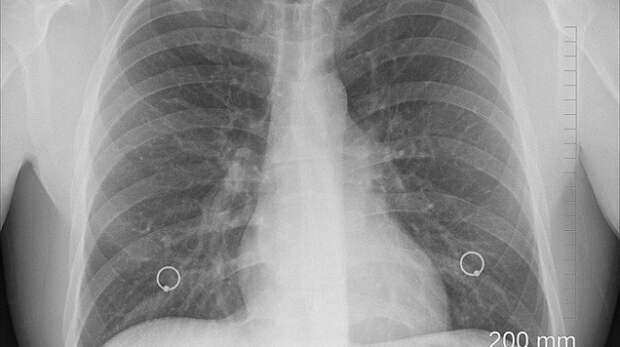

Врачи Филиала ФНКЦ и Крымского республиканского клинического центра фтизиатрии в ходе акции посетят Массандру, Никиту, Даниловку, Отрадное, Краснокаменку, Гаспру, Симеиз, Голубой Залив, Кацивели, Береговое.

Пройти диагностику сможет любой желающий - обследование проводится бесплатно.

Уточнить график работы комплекса для записи на прием можно на официальной странице Филиала ФНКЦ в социальных сетях, а также по телефонам контакт-центра 8 (3654) 55-59-73, 8 (3654) 55-50-81.